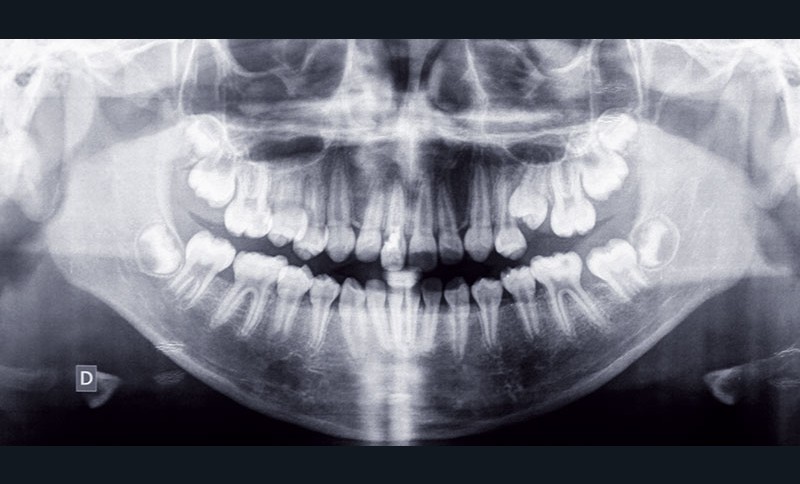

Situation clinique (fig. 1 à 9)

Orlhane B., 10 ans, est adressée à l’unité fonctionnelle d’orthodontie de l’hôpital Bretonneau par son dentiste suite à un traumatisme sur la 11. Le trait de fracture est infra-osseux et ne permet pas la réalisation d’une restauration prothétique de cette dent. Le praticien nous demande de réaliser une extrusion orthodontique afin d’égresser la dent sans que son parodonte suive le mouvement dentaire et d’augmenter ainsi l’espace biologique. La longueur radiculaire permet ce mouvement (rapport couronne/racine postextrusion inférieur à 1) et un traitement à l’hydroxyde de calcium est réalisé transitoirement durant le déplacement orthodontique. L’obturation finale sera réalisée une fois que les limites du trait de fracture seront supra gingivales et permettront la mise en place d’un champ opératoire étanche.

À l’examen clinique, Orlhane présente une classe I biproalvéolie aggravée par 11 fracturée et 25 enclavée et une classe II canine légère gauche. Cette malocclusion est associée à une classe II squelettique par promaxillie sur un schéma facial hyperdivergent. Il est décidé de ne pas traiter la biproalvéolie et la classe II squelettique modérées d’origine ethnique chez cette patiente.